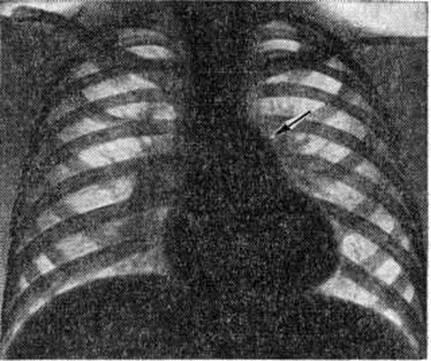

Рентгенограмма грудной клетки при аортальном стенозе: тень сердца имеет форму башмака (аортальная конфигурация) с увеличенным левым желудочком; (указан стрелкой), верхушка закруглена (гипертрофия левого желудочка).

При рентгенологическое исследовании у детей тень сердца нормальных размеров или с признаками гипертрофии левого желудочка. При высоком конечно-диастолическом давлении в левом желудочке и левом предсердии отмечаются застойные явления в прикорневых отделах лёгких. Может быть расширена восходящая часть аорты (постстенотическая дилатация). У детей с выраженным стенозом рентгенологически определяется аортальная конфигурация сердца (рисунок 4) и усиленный легочно-сосудистый рисунок.